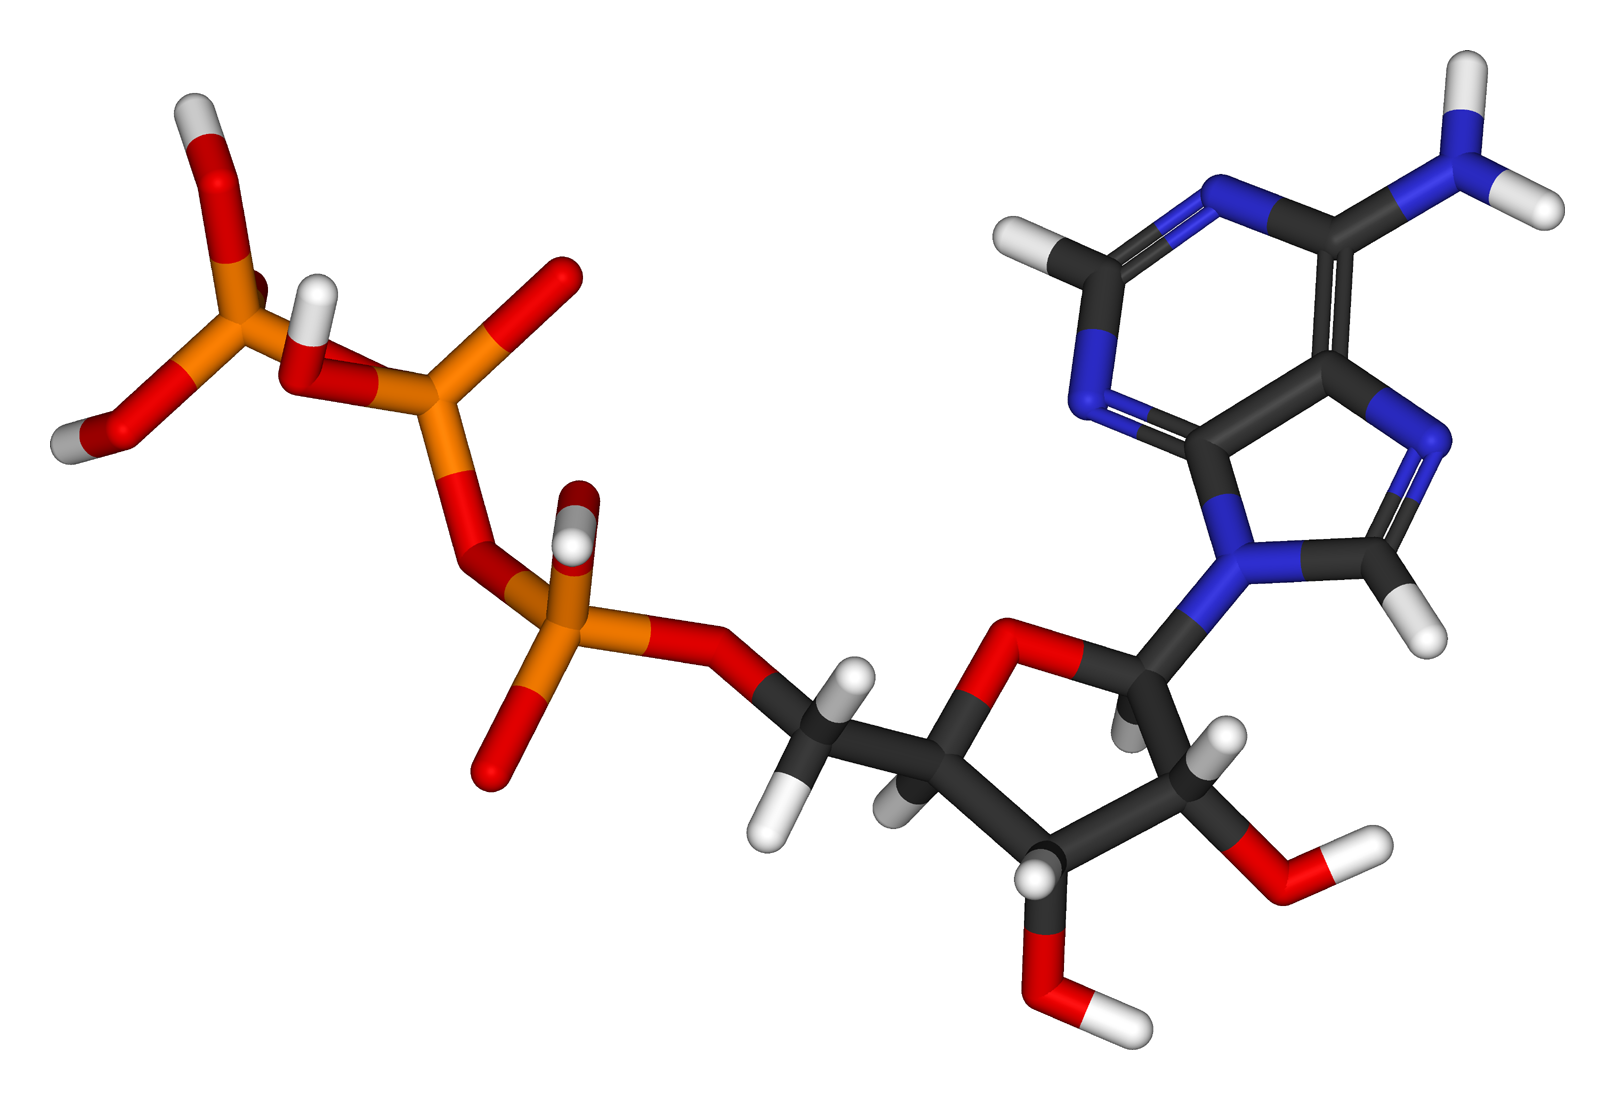

Le corps des êtres vivants tels que des animaux et des hommes possède une incroyable quantité de cellules, environ 100 000 milliards au total. Par conséquent, il est en état de renouvellement cellulaire permanent, à partir de la naissance jusqu’à la mort. Il est en quelque sorte constamment remis à neuf.

Pratiquement tous les organes, tous les tissus et toutes les cellules sont soumis à ce renouvellement cellulaire permanent et vont être complètement régénérés plusieurs fois dans une vie, à une fréquence plus ou moins élevée en fonction des cellules. Ce qui fait qu’au bout du compte, l’immense majorité des cellules et des organes sont plus jeunes que l’individu lui-même.

Ce vaste écosystème cellulaire – qui est finalement notre organisme – contient environ 250 types de cellules différentes. La grande majorité est soumise au renouvellement cellulaire, sauf quelques exceptions, comme, par exemple, les neurones et les cellules cardiaques où le renouvellement est très lent ou quasi inexistant.